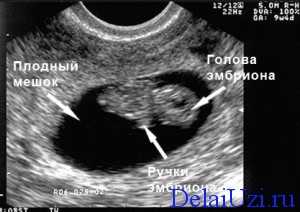

УЗИ 9 недель беременности: фото, норма

На 9 неделях беременности малыш уже становится явственно похожим на человека. У него есть голова, ручки и ножки, животик, спинка и все, что еще положено иметь малышу. Конечно, все органы ребенка тотально недоразвиты, но их развитие – лишь вопрос времени. В длину он достигает 2 см.

По показаниям проверяется количество прогестерона, низкое значение может спровоцировать прерывание беременности. На 9 неделе можно пройти УЗИ, если женщина не сделала его ранее. При выполнении ультразвуковой диагностики видны сердцебиение малыша, его движения. Исследование помогает оценить состояние эмбриона и матки, выявить патологии развития, определить замершую беременность.

- Размеры малыша уже в пределах 1,3-1,6 см, если делать замер копчико-теменного размера.

- У него уже сформированы пальчики на ручках и ножках.

- Происходит формирование костных тканей и мышц.

- Растет и развивается плацента и пуповина. На ультразвуке обязательно оценивают состояние этих важных параметров развития беременности.

Теперь ребенок может реагировать на раздражители мира, который окружает его маму. Так во время проведения УЗД, когда осуществляется незначительно надавливание на стенку живота или введение во влагалище датчика он начинает активные движения.

На этом сроке сердце – уже почти сформированный орган, число ударов за минуту около 180. Если необходимо уточнит количество сокращений мышцы, то назначают проведение допплерометрии.

Лицо уже почти как у настоящего человека, можно увидеть ушные раковины. Развиваются внутренние органы, которые, конечно же, пока слишком малы для проведения их исследования. Причем рост органов настолько интенсивный, что они могут выпячиваться – не стоит волноваться на этом сроке – это нормально. Они станут на свои места только к концу первого триместра.

Важное событие это недели – формирование мозжечка и гипофиза. Первый отвечает за координацию движения, второй за продуцирование гормонов. Уже происходит закладка надпочечников, они будут главными при выработке адреналина. Также формируются лимфоузлы, молочные железы, половые органы. О поле ребенка говорить еще рано, он еще слишком мал, чтобы можно было что-то рассмотреть.

В ходе УЗД в 9 недель, если оно назначается, происходит мониторинг состояния матки и ее придатков. Важным событием является начало регресса желтого тела, ведь плацента уже практически перебрала на себя его функции. Еще может просматриваться желточный мешочек, ведь он пока что выполняет функцию кровотворения.

Ваш будущий ребенок сейчас официально будет именовоться вплоть до родов не эмбрионом, а плодом. Его маленький эмбриональный хвостик исчез. На УЗИ плода в 9 недель беременности размеры соответствуют средней оливке, это 14-15 мм, а у плода ужеимеются крохотные ручки и ножки, пальцы на которых все еще перепончатые. Начинают формирование кости и сухожилия. Пуповина и плацента формируются и растут, на УЗИ плода в 9 недель беременности измеряется толщина хориона (плаценты), определяется пуповина. Плод способен отвечать движениями на прикосновения к передней брюшной стенке в проекции матки, например при проведении УЗИ при беременности. Сердце плода становиться достаточно большим и практически сформированным, частота сердечных сокращений достигает 180 в этот период, что можно отметить при УЗИ плода в 9 недель беременности с применением допплера. Лицо плода становится более сформированным, уши более выступающими, продолжают совершенствоваться печень, селезенка и желчный пузырь. Конечно, все эти органы еще невозможно увидеть на УЗИ плода в 9 недель беременности, это будет возможно несколько позже. Внутренние органы плода в девять недель беременности еще могут выпячиваться в виде пупочной грыжи.Это можно увидеть на УЗИ плода в 9 недель беременности и это нормально для данной стадии развития. Полное возвращение внутренних органов в пределы передней брюшной стенки плода в норме происходит после 10 недель беременности. При УЗИ плода в девять недель беременности обязательно оцениваются яичники. Желтое тело при УЗИ яичников начинает свое обратное развитие, так как формируется полноценная плацента, способная взять на себя полностью гормональную поддержку развивающейся беременности. Желточный мешок пока все еще визуализируется, он еще не выполнил свою основную кроветворную функцию. Иногда его можно даже увидеть при УЗИ плода в 12 недель беременности.